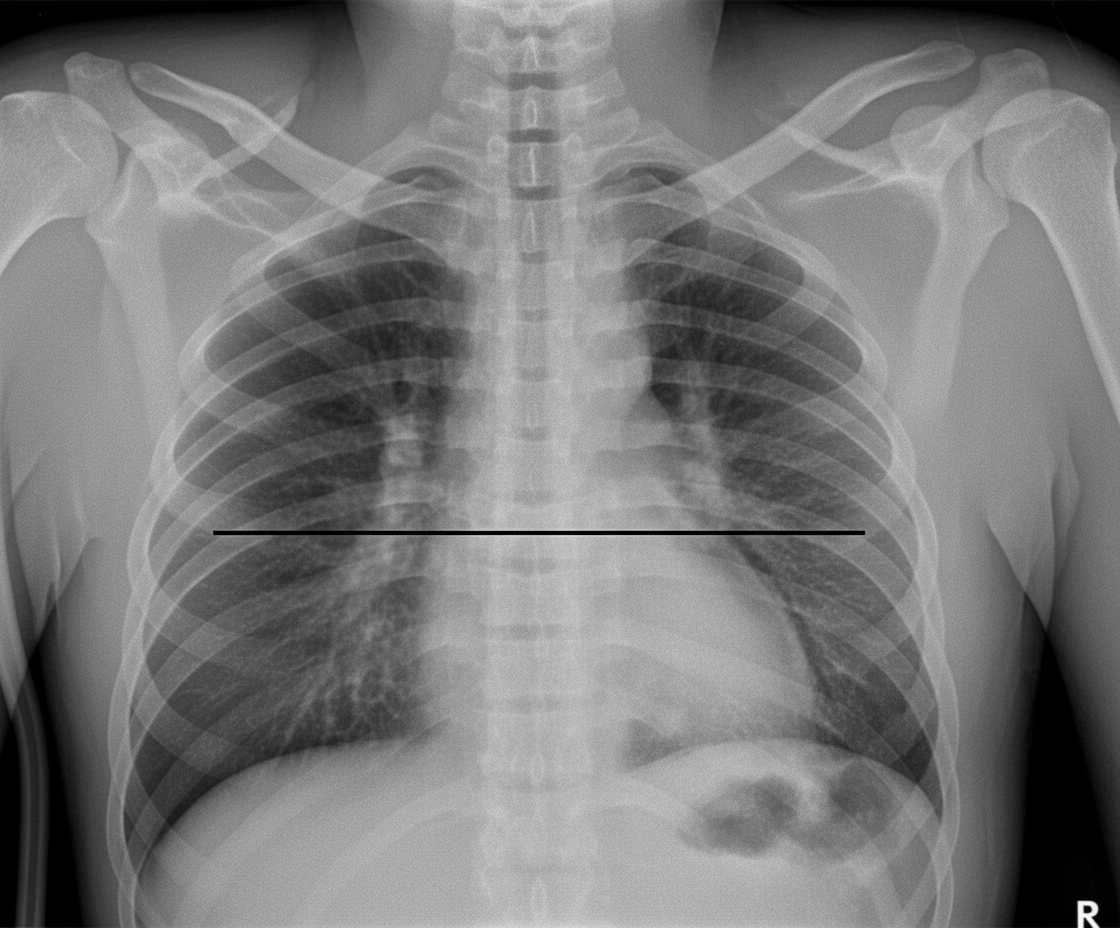

A 45-year-old male presents with sudden onset shortness of breath and chest pain. A chest X-ray is obtained. What is the most likely diagnosis based on the image?

Explanation: ***Pneumothorax*** - The chest X-ray shows several classic signs of a pneumothorax: **absent vascular markings** in the right lung field (indicated by red markings), a **deep sulcus sign** (blue arrow), and a visible **visceral pleural line** (yellow line) separating the collapsed lung from the chest wall. - The sudden onset of **shortness of breath** and **chest pain** in a 45-year-old male is consistent with the clinical presentation of a spontaneous pneumothorax. *Pleural Effusion* - A pleural effusion would typically present as a **blunting of the costophrenic angle** and a **meniscus sign** (concave upper border of fluid), which are not the primary features seen here. - While fluid can cause chest pain and shortness of breath, the distinct visceral pleural line and absent lung markings point away from an effusion as the primary diagnosis. *Pulmonary Edema* - Pulmonary edema is characterized by **cardiomegaly**, **perihilar haziness**, **Kerley B lines**, and often **bilateral effusions**, none of which are evident on this X-ray. - The clear lung field with absent markings is contrary to the diffuse alveolar or interstitial opacities seen in pulmonary edema. *Consolidation* - Consolidation, typically due to pneumonia, shows as a **lobar or segmental opacification** with **air bronchograms**, indicating fluid or cells filling the alveoli while the airways remain open. - This image clearly demonstrates a collapsed lung with air in the pleural space, not opacified lung tissue or air bronchograms.